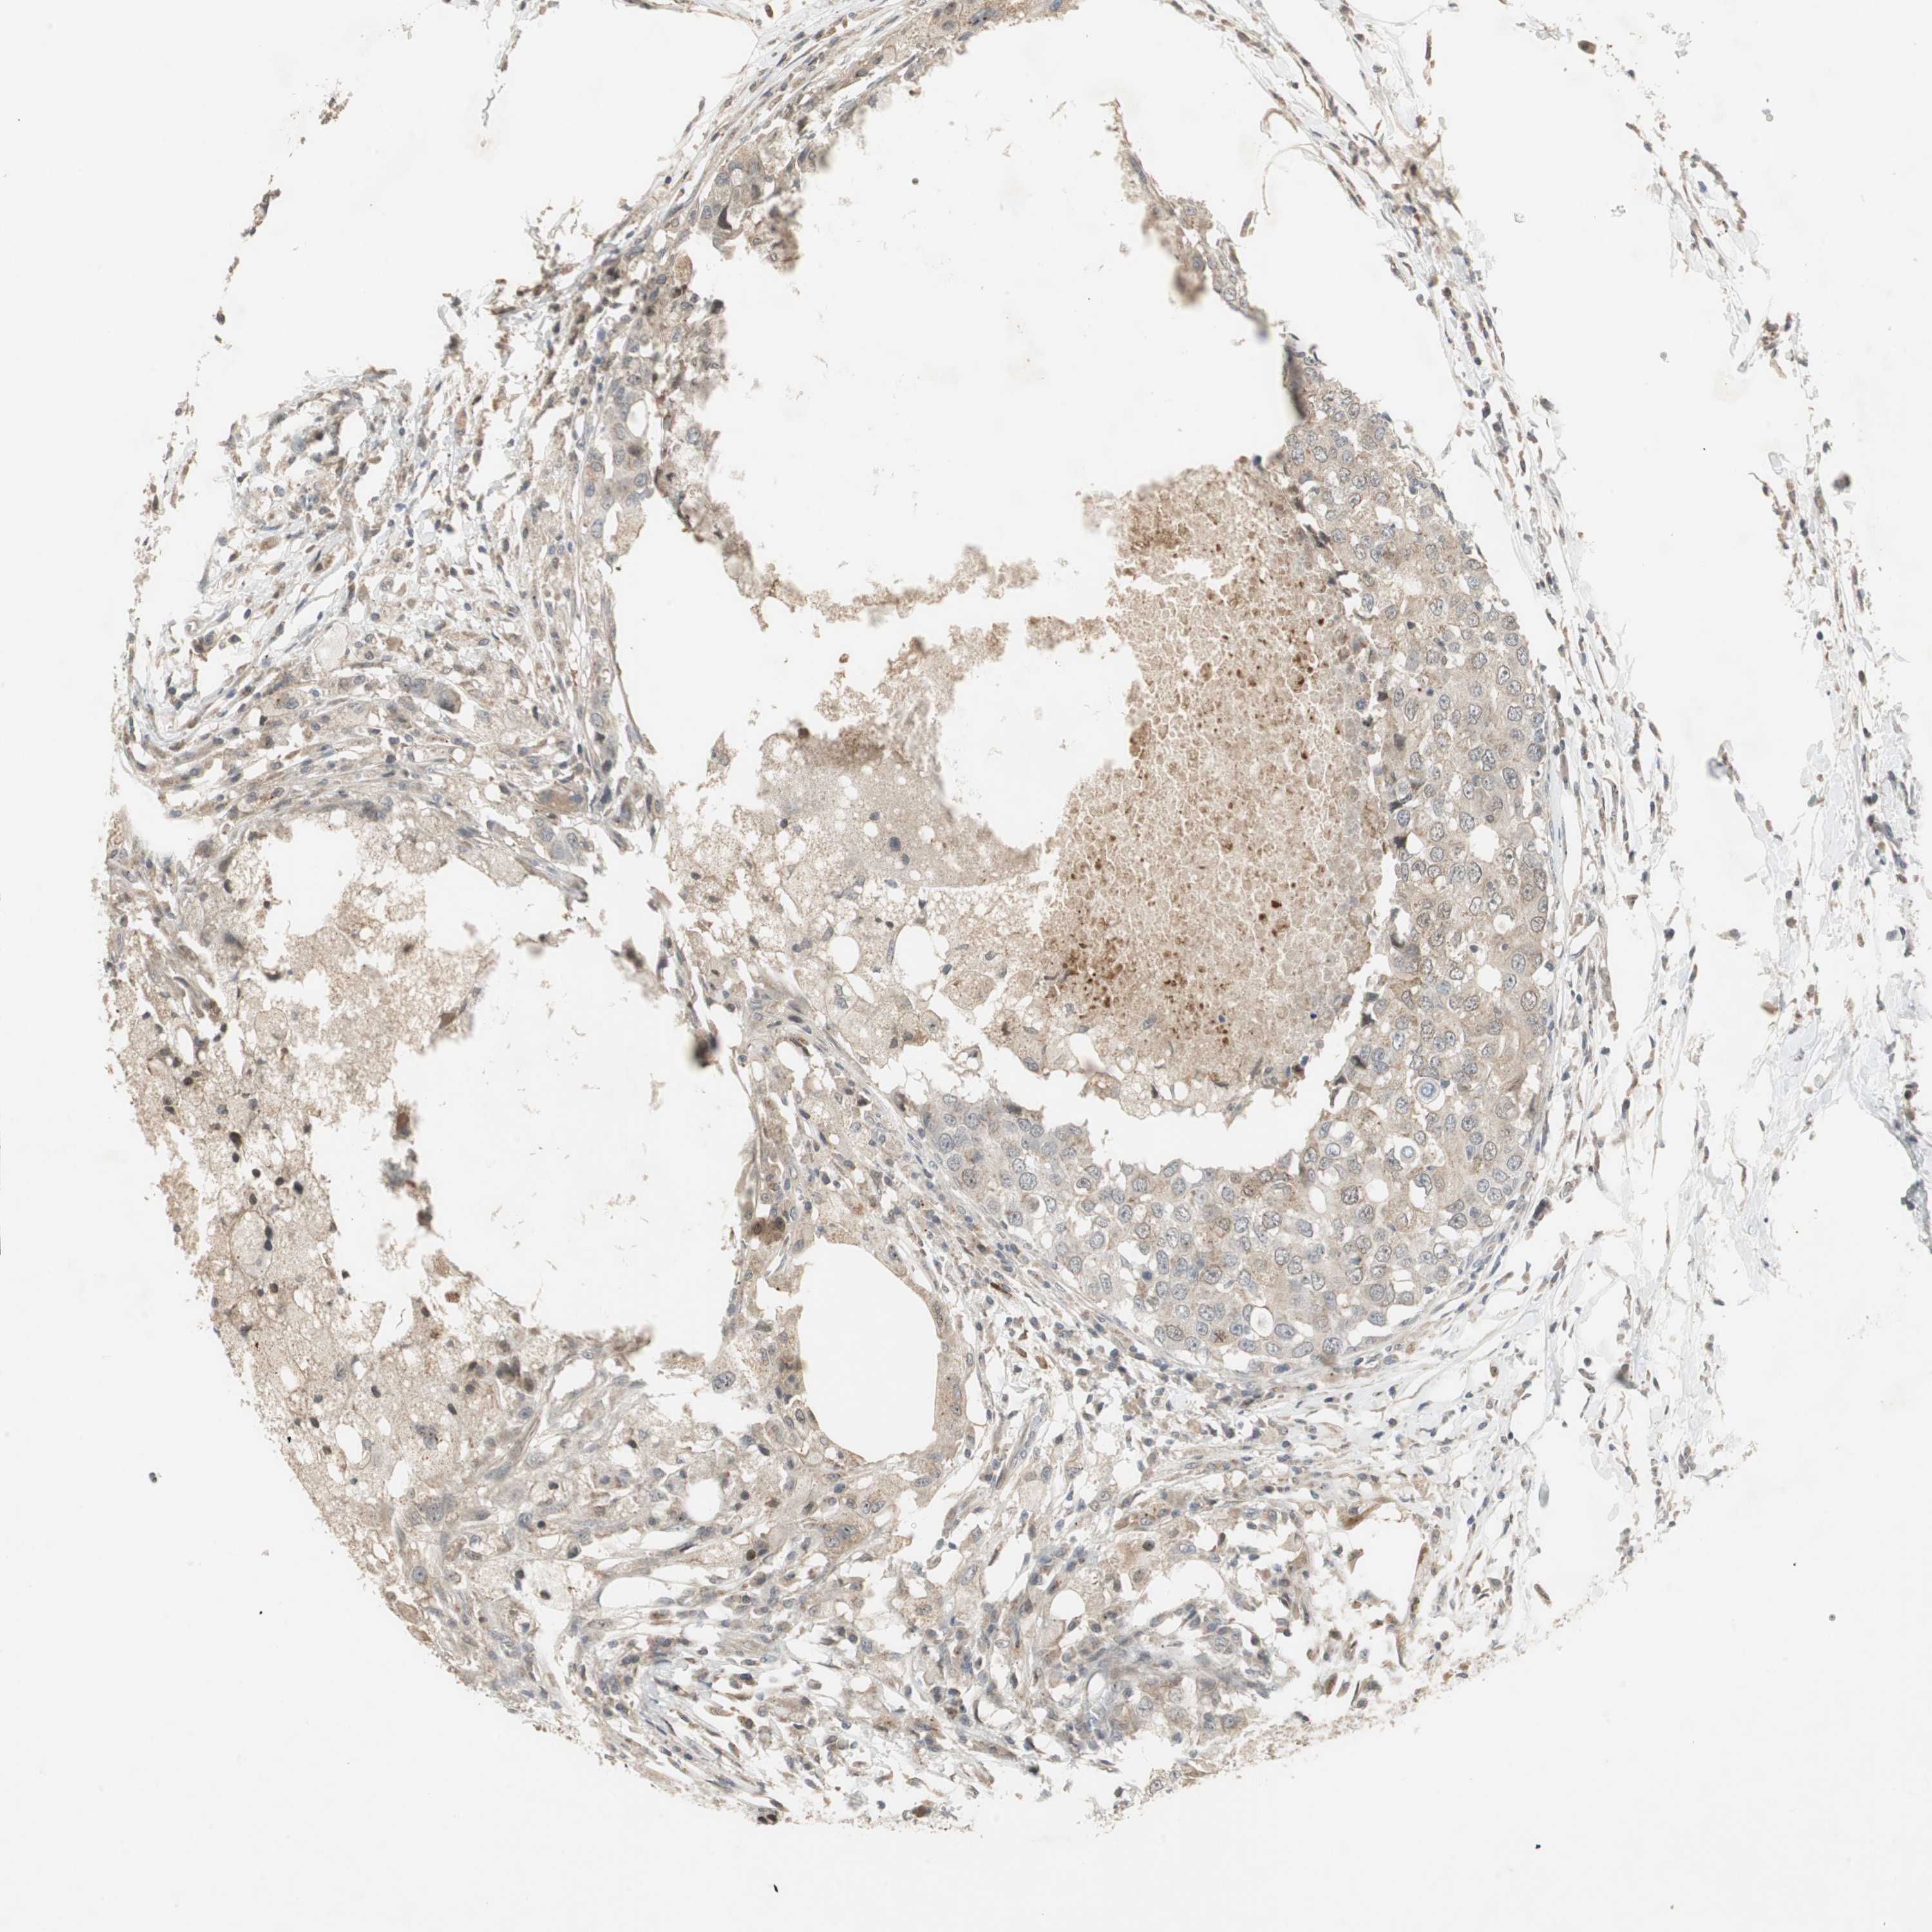

CANCER BREAST CANCER Show tissue menu

BRCA TCGA BRCA VALIDATION PROTEIN EXPRESSION

ANTIBODIES